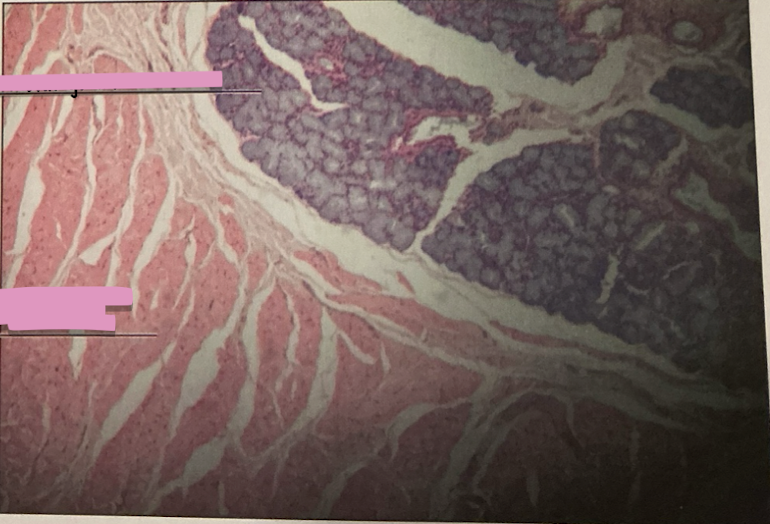

lympatic vessel valve

lymph node

thymus

thymus

where does development of T cells occur?

Hassall’s Corpuscle

___________ sites accumulate dead T cells & involved in development of reg. T cells